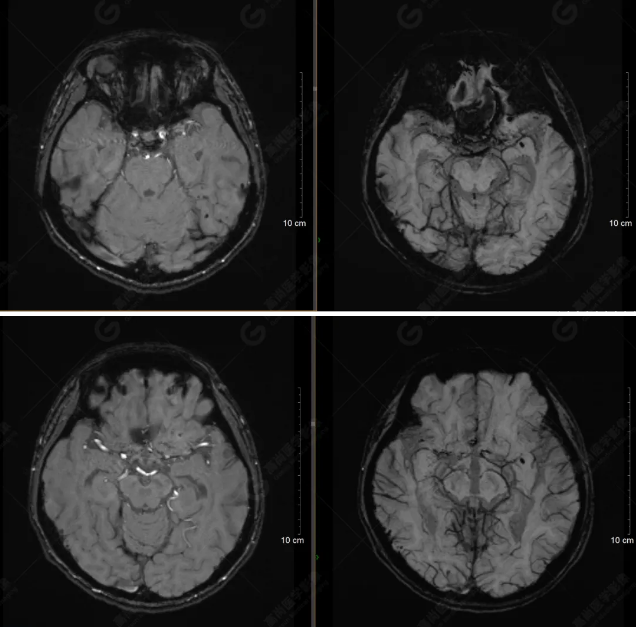

以下是平掃T2WI及FLAIR序列:

雙側(cè)大腦半球?qū)ΨQ,灰白質(zhì)對比正常,顱內(nèi)未見異常信號影。腦室系統(tǒng)未見擴(kuò)大,中線結(jié)構(gòu)居中。腦溝、裂未見增寬。幕下小腦、腦干未見異常。矢狀位示垂體形態(tài)、大小級信號未見異常。所示左側(cè)乳突內(nèi)見多發(fā)短T1長T2信號影。

顱腦MRI平掃未見明顯異常,左側(cè)乳突內(nèi)積血,建議補(bǔ)充SWI檢查。